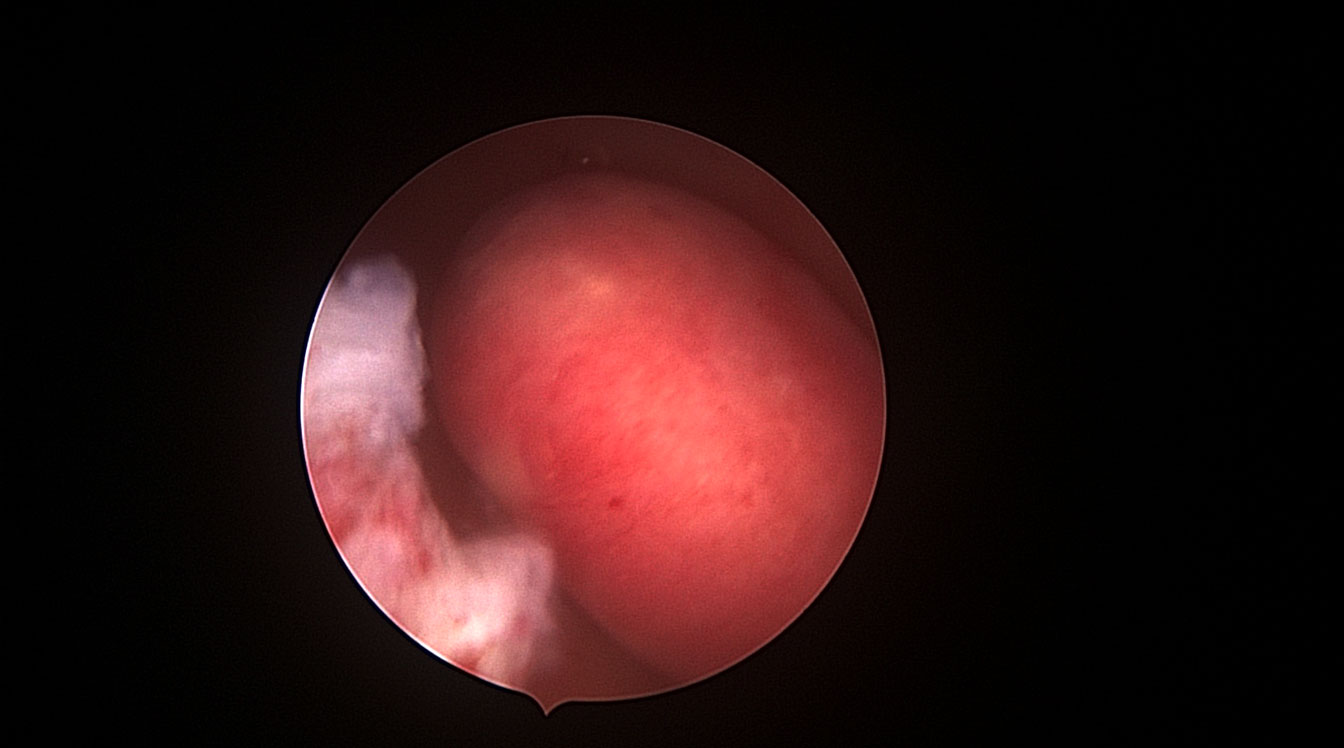

Infertilitate

Histeroscopia reprezintă o etapă importantă în cadrul investigațiilor efectuate pacientelor ce prezintă diagnosticul de infertilitate. Histeroscopia poate identifica modificări subtile ale cavității uterine, ce nu pot fi diagnosticate prin ecografie, ceea ce face ca această inervenție să devină extrem de utilă la pacientele cu infertilitate. Un exemplu poate fi reprezentat de inflamația cronică a endometrului, situație numită endometrită (Fig. 9, 10).